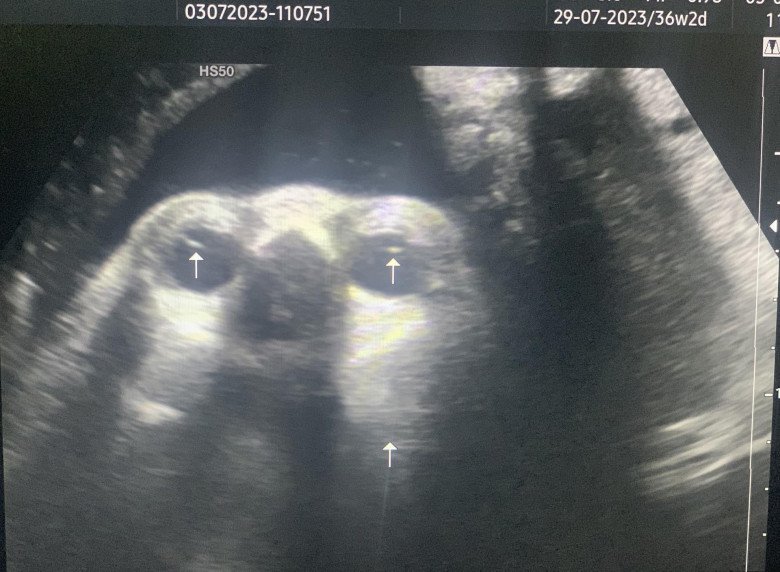

Theo đó, bác sĩ Trung kể rằng, mới đây, một sản phụ mang thai lần 2 được 34 tuần đến viện siêu âm. Tuy nhiên khi thăm khám và siêu âm thai cho sản phụ trên, anh đã phát hiện thai nhi bị đục thủy tinh thể bẩm sinh. Sản phụ khi biết thai nhi mắc dị tật này đã ôm mặt khóc dù cho biết gia đình chồng cũng có tiền sử bị bệnh này (bố chồng, chồng và con đầu của anh chị).

Bác sĩ Giang khẳng định, đục thể thủy tinh bẩm sinh là một dị tật bẩm sinh hiếm gặp của mắt xảy ra trước khi sinh hoặc ngay lúc vừa mới sinh. Thay vì thủy tinh thể trong suốt như bình thường thì 2 mắt của thai nhi sẽ lại bị đục và khiến cho ánh sáng tới mắt bị cản trở.